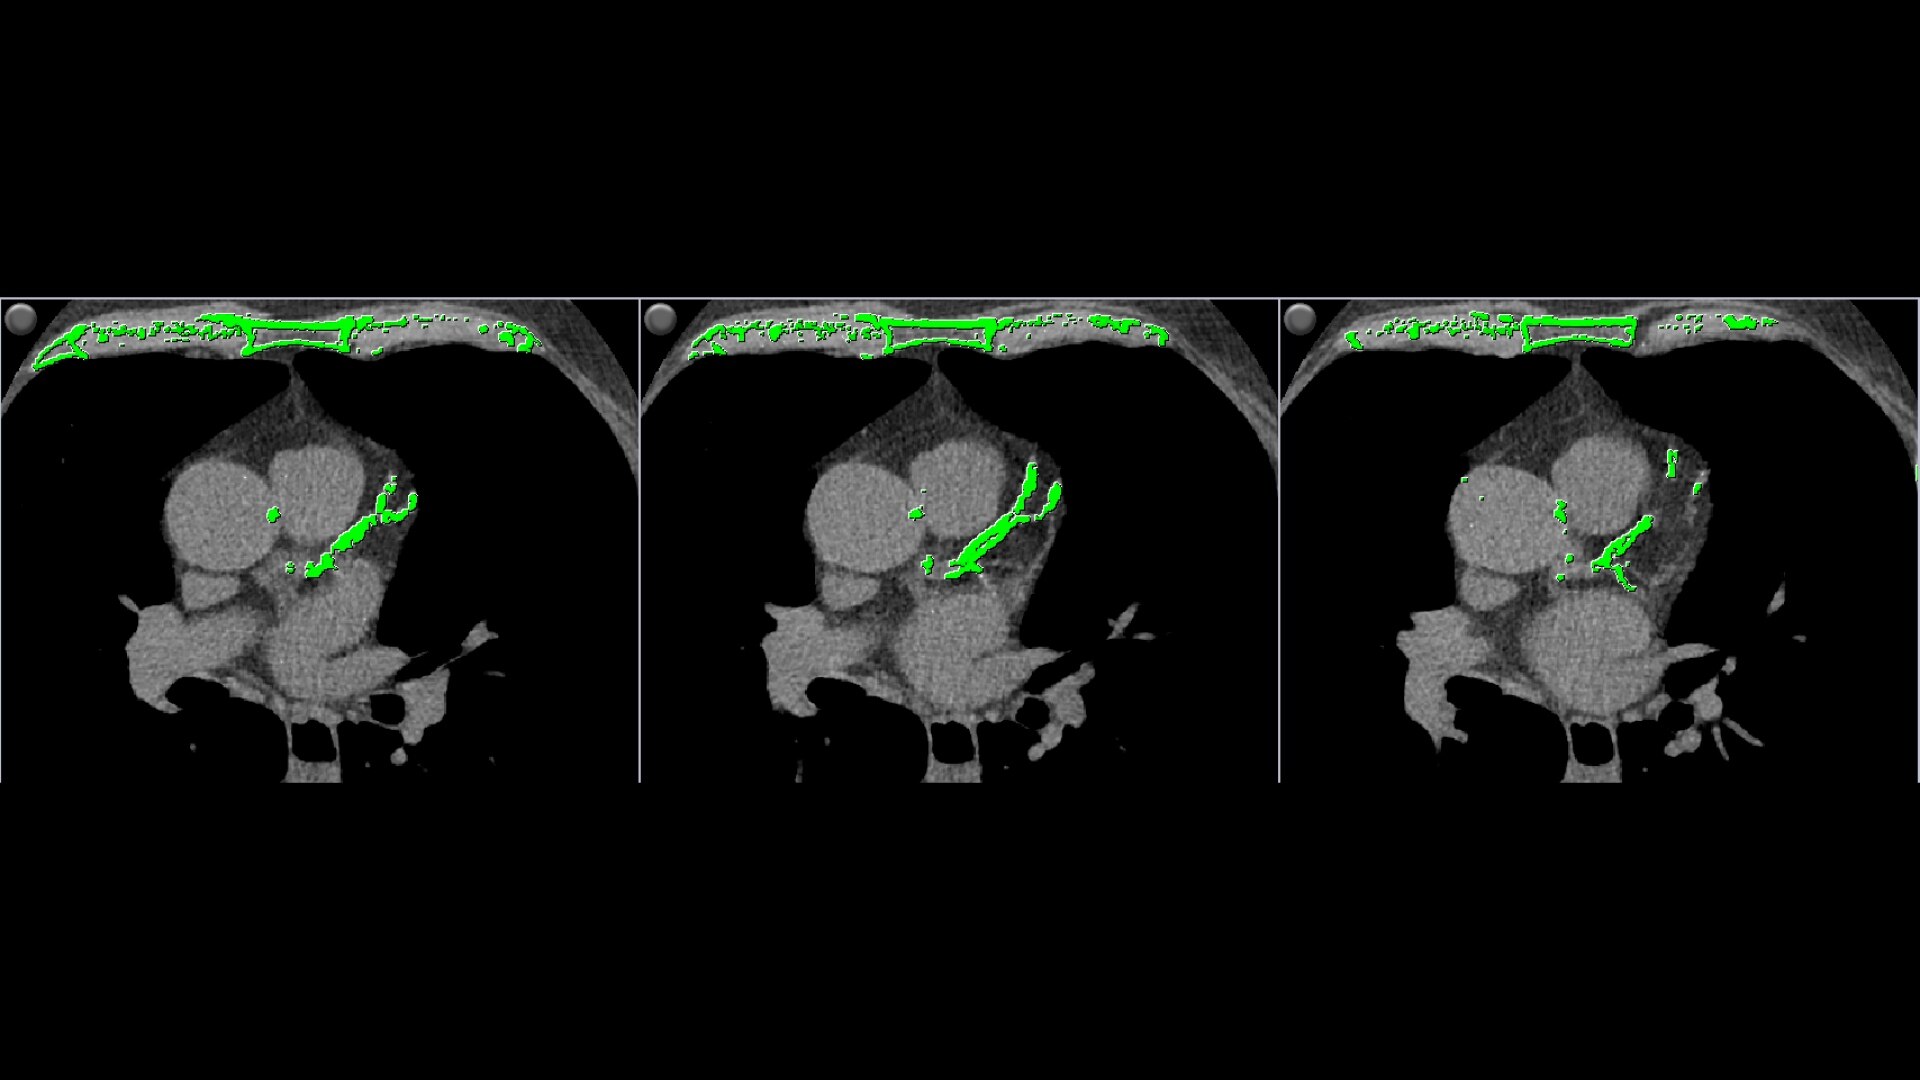

• Automatically detects calcium and highlights it in green

• Volume scoring calculates volumes (mm3) of calcified plaque above the 130 HU threshold

• Mass scoring calculates mass (mg) of calcified plaque above the 130 HU threshold

• Individual and aggregate scores are computed for each artery type